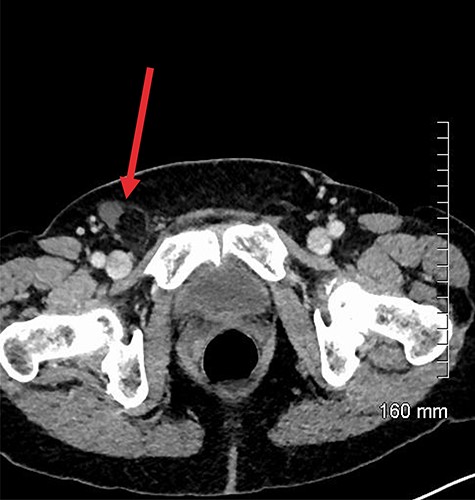

An incarcerated femoral hernia was diagnosed clinically and previous hematological investigations and imaging studies were reviewed. Full blood count, urea and electrolytes and liver function tests were within normal limits. Inflammatory markers including C-reactive protein had not been tested for preoperatively. The patient’s staging computed tomography (CT) thorax, abdomen and pelvis (performed a month before surgery) had shown fluid in the right inguinal region, appearing to lie within a small hernia (Fig. 1). A decision was made by the treating team to proceed with a joint procedure. The patient was consented for simultaneous mastectomy with axillary clearance and hernia repair.

Axial contrast-enhanced CT showing hernial sac containing fat and simple fluid but no appendix (red arrow).